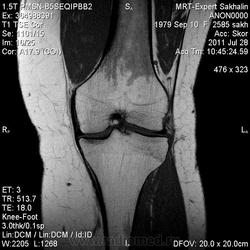

Коленный сустав

Подглядела случай у коллеги.

Что это может быть?

P.S. В костях - это, скорее всего, резидуальный красный костный мозг.

участки гемопоэтического костного мозга